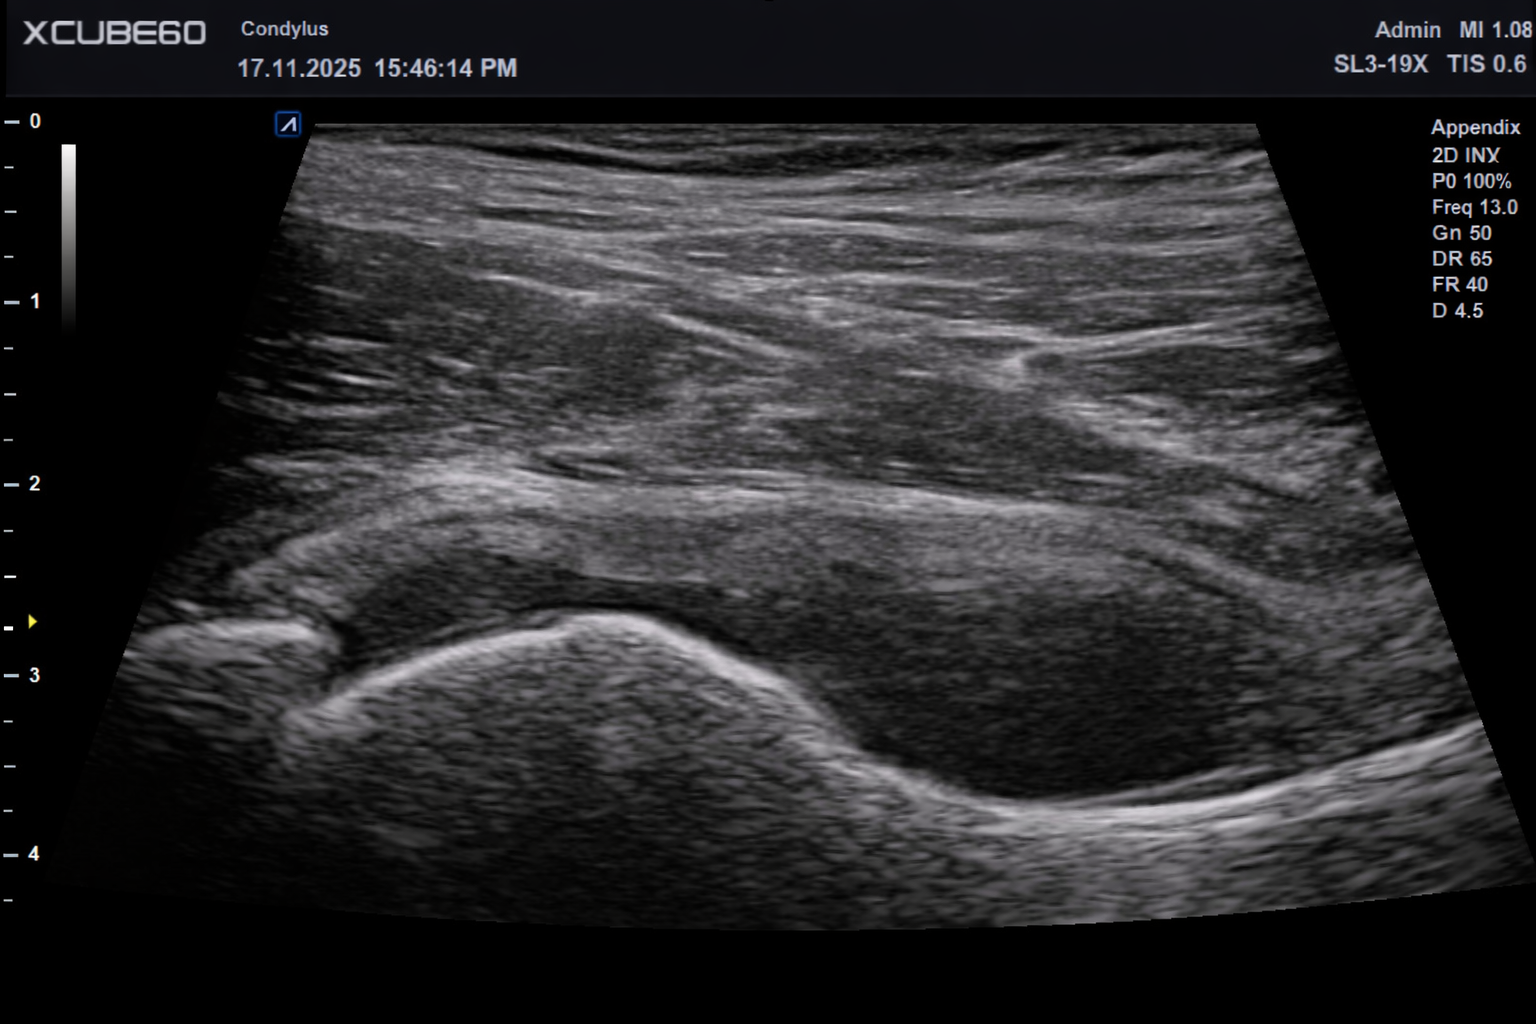

USG narządu ruchu

Czym różni się badanie USG stosowane w trakcie fizjoterapii i osteopatii od wyników badania przyniesionych przez pacjenta? Zasadnicza różnica tkwi w tym, że w gabinecie fizjoterapii przeprowadzana jest diagnostyka w czasie rzeczywistym, w tym diagnostyka czynnościowa, która pozwala stwierdzić, jak narząd zachowuje się w ruchu.